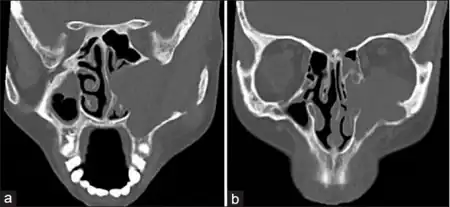

Diagnosis

Esthesioneuroblastoma can resemble small blue cell tumors like squamous cell carcinoma, sinonasal undifferentiated carcinoma, extranodal NK/T cell lymphoma, nasal type, rhabdomyosarcoma, Ewing/PNET, mucosal malignant melanoma and neuroendocrine carcinomas (NEC) that occur in the intranasal tract.[1] Compared to other tumors in the region, esthesioneuroblastoma has the best prognosis, with an overall five-year survival rate of 60–80%.[1] Fewer than 700 cases have been documented in the United States alone.[12] Esthesioneuroblastoma is characterized by neurofibrillary stroma and neurosecretary granules that are not seen concurrently by any other pathologies in the region.[1] Histological tests such as keratin, CK5/6, S-100 protein or NSE can be run to further differentiate esthesioneuroblastoma from other tumors.[1]